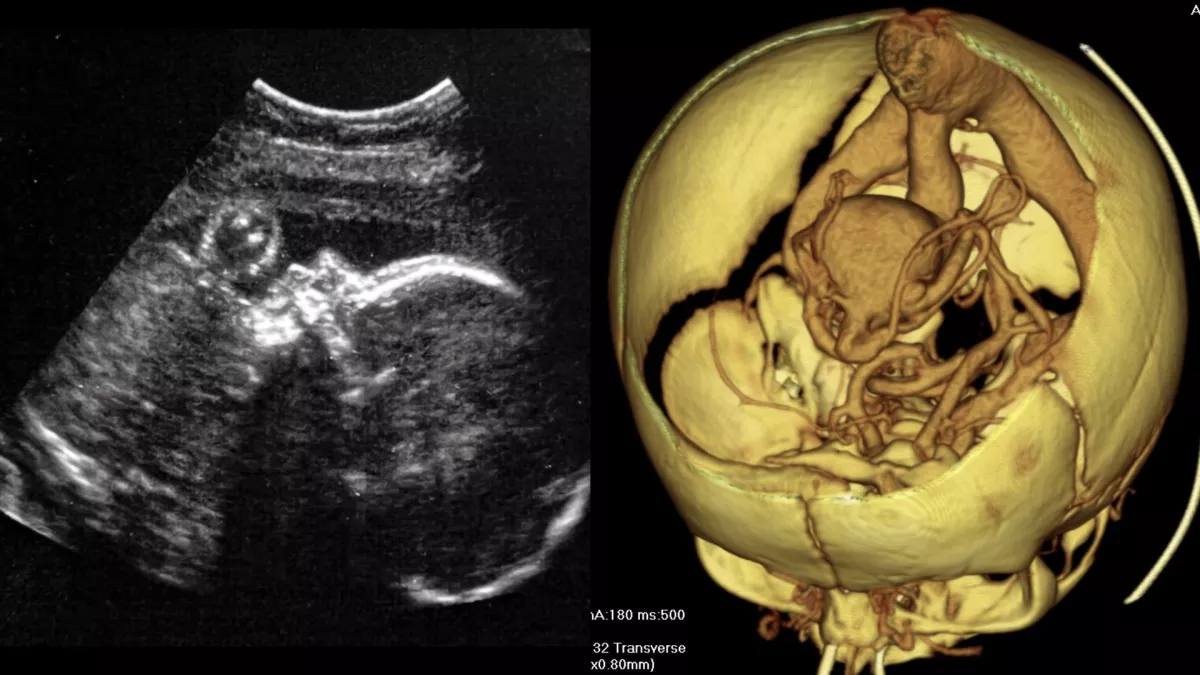

Америк эмч нар хэвлийд буй хүүхдийн тархинд хагалгаа амжилттай хийжээ